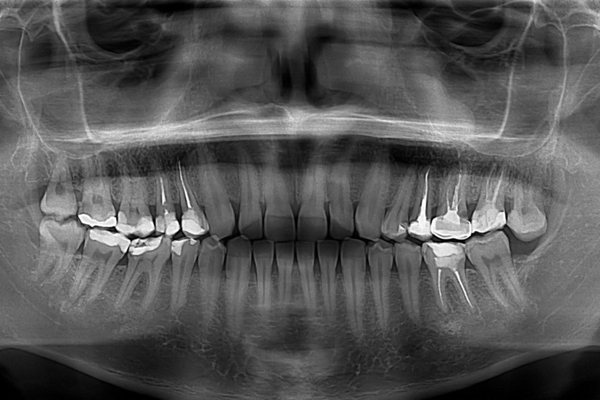

Radiografia

Panorâmica

A Panorâmica é uma radiografia extraoral que fornece uma imagem bidimensional de toda a boca em uma única tomada. Ela permite uma visão geral das arcadas dentárias, maxila, mandíbula, seios da face e articulações temporomandibulares (ATM). É um exame de triagem fundamental para a avaliação inicial, detecção de cáries extensas, cistos, tumores, avaliação de dentes do siso e análise do suporte ósseo, sendo a base de muitos diagnósticos na odontologia.